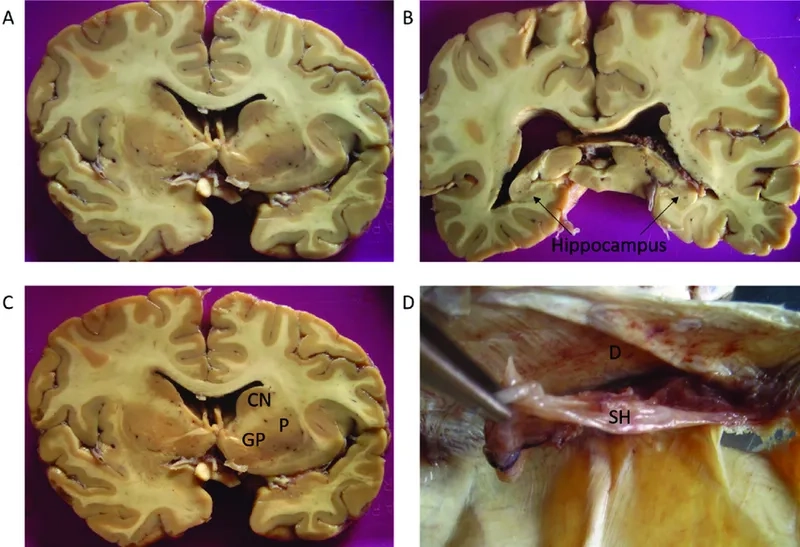

Visualizing concepts related to CTE

The challenges surrounding a definitive CTE diagnosis in the living

The complex process of a post-mortem CTE diagnosis